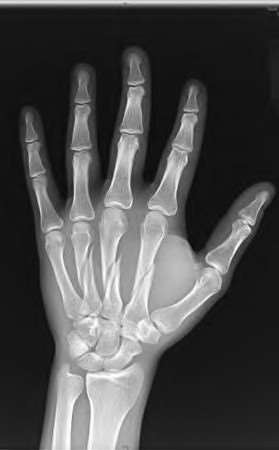

A 50-year-old woman is diagnosed with carpal tunnel syndrome. She is prescribed a cock-up wrist splint at 30 degrees of extension to wear at night. This splint has what effect on the carpal tunnel?